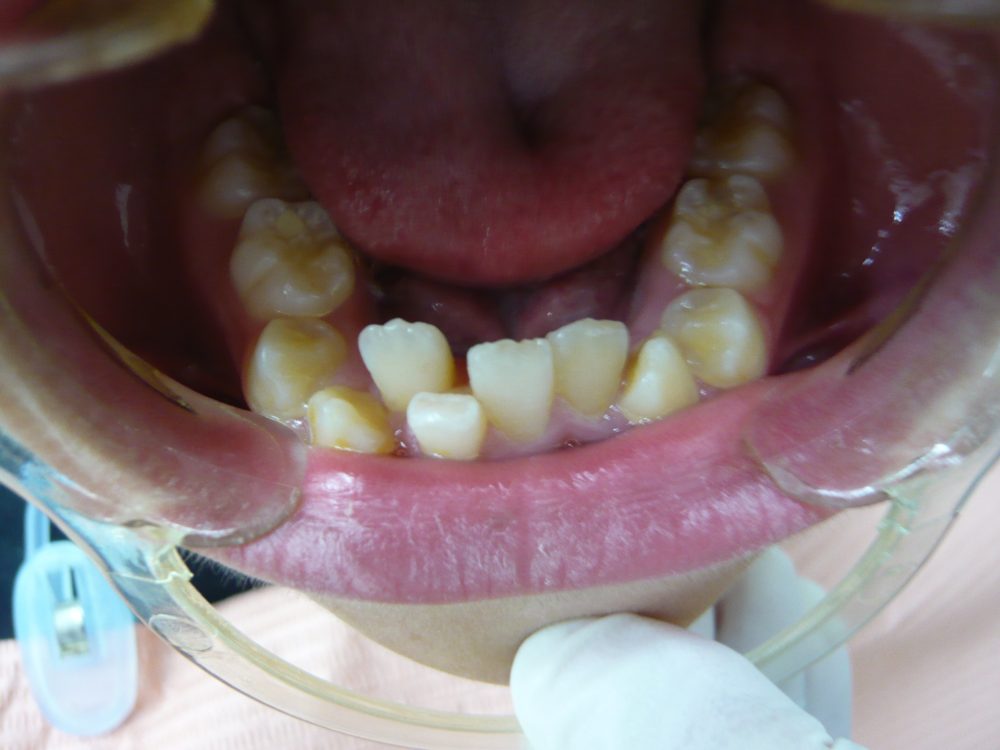

叢生(でこぼこ)

15歳 男性 9か月

11歳 女の子 6か月半

19歳 男性 3年9か月

15歳 2年7か月 女の子

46歳 女性 1年1ヵ月

13歳 女の子 5年1か月

13歳 男の子 1年8ヶ月

26歳 女性 1年6か月

11歳 女の子 9か月

13歳 女の子 3年6か月